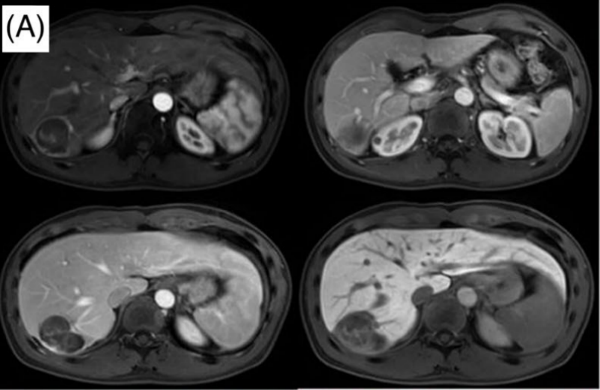

图A Y90-SIRT治疗后3月EOB-MRI:癌灶显著缩小(D=5.2 cm),癌栓消失